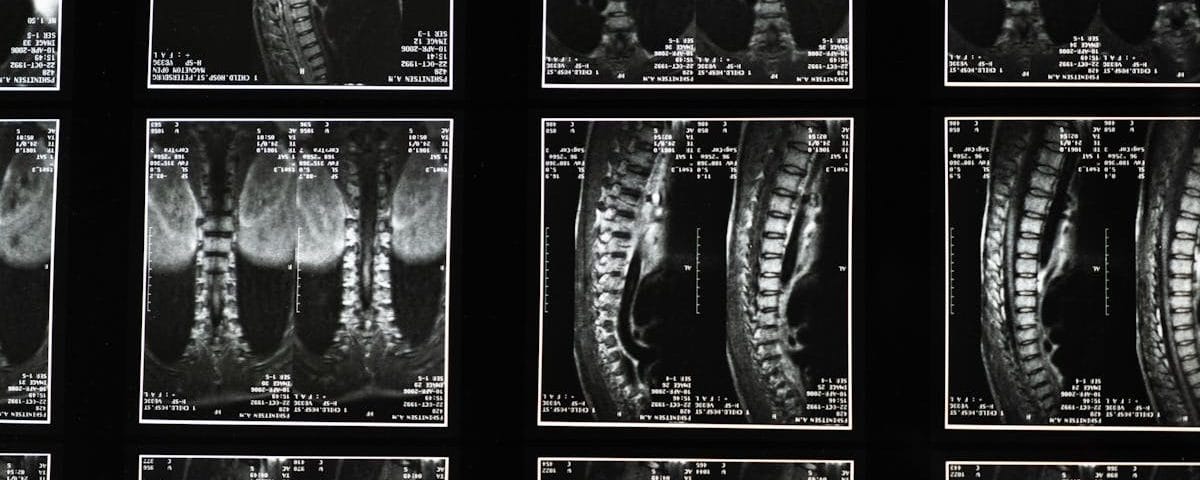

La décompression vertébrale est une approche thérapeutique visant à réduire la pression exercée sur les disques intervertébraux et les nerfs spinal. Cette technique utilise des appareils spécialisés pour créer un environnement propice à la guérison. Les experts en santé choisissent cette méthode car elle réduit de manière significative les douleurs et favorise la circulation sanguine vers les zones affectées.

Comprendre la décompression vertébrale

La décompression vertébrale se réfère à des techniques qui visent à soulager la pression sur les disques intervertébraux et les nerfs. Cette approche est souvent recommandée pour les personnes souffrant de hernies discales, de douleurs lombaires, ou de douleurs cervicales chroniques. En relâchant la pression sur les nerfs et en favorisant une meilleure circulation sanguine autour des structures vertébrales, cette méthode contribue à réduire l’inflammation et à améliorer la mobilité.